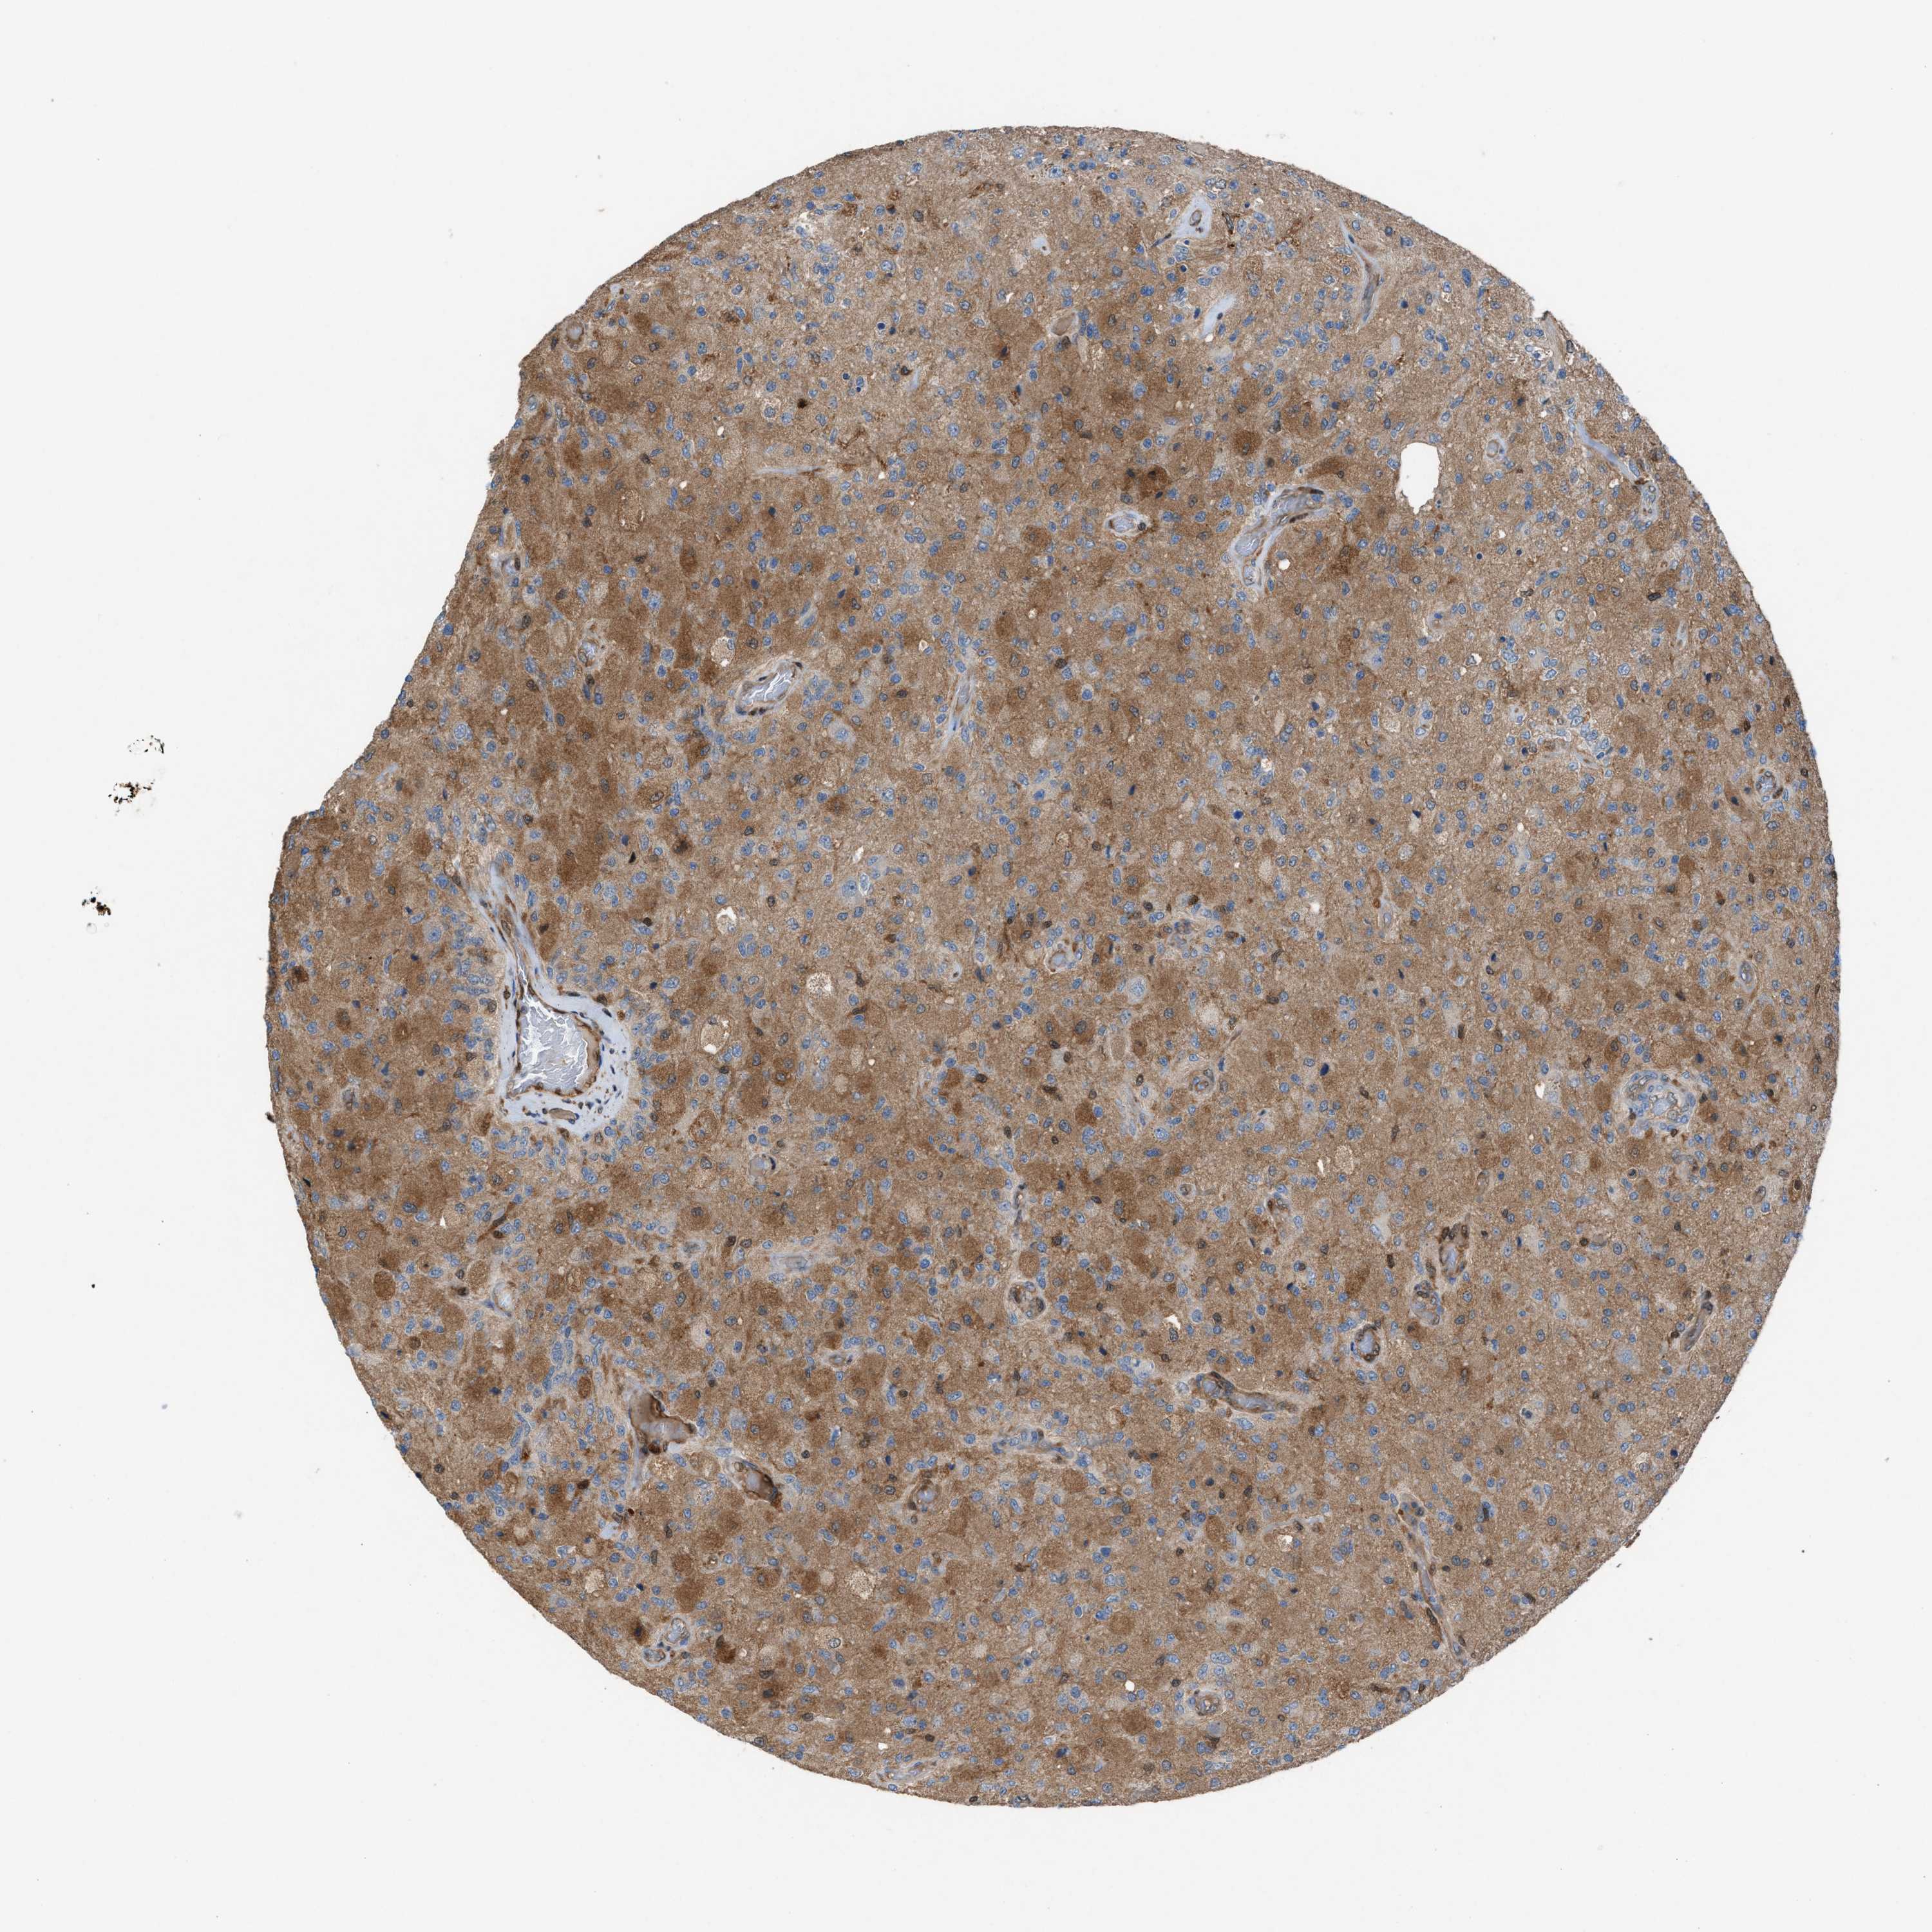

GLIOMA - Protein expressioni

A mouse-over function shows sample information and annotation data. Click on an image to view it in a full screen mode. Samples can be filtered based on level of antibody staining by selecting one or several of the following categories: high, medium, low and not detected. The assay and annotation is described here.

Note that samples used for immunohistochemistry by the Human Protein Atlas do not correspond to samples in the TCGA dataset.

Antibody stainingi

Antibody staining in the annotated cell types in the current human tissue is reported as not detected, low, medium, or high, based on conventional immunohistochemistry profiling in selected tissues. This score is based on the combination of the staining intensity and fraction of stained cells.

Each image is clickable and will lead to virtual microscopy that enables deeper exploration of all samples and also displays staining intensity scores, fraction scores and subcellular localization as well as patient and tissue information for each sample.

Antibody HPA021545

Antibody HPA021849

Staining

High

Medium

Low

Not detected

Intensity

Strong

Moderate

Weak

Negative

Quantity

>75%

75%-25%

<25%

None

Location

Nuclear

Cytoplasmic/membranous

Cytoplasmic/membranous,nuclear

Glioma, malignant, High grade

Glioma, malignant, Low grade